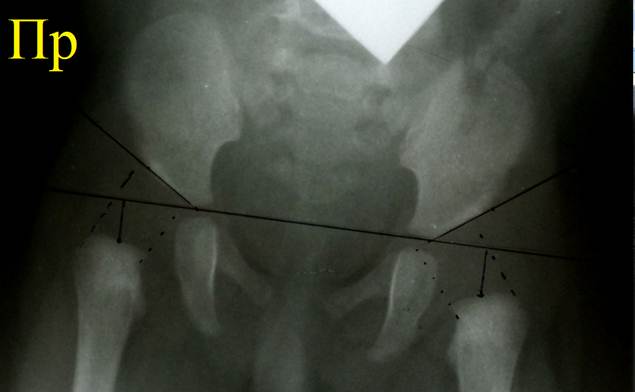

Начинают

расчерчивание с базовой линии Хильгенрейнера: проводят горизонтальную линию,

касающуюся нижних краев теней подвздошной кости. Затем проводят линии,

касательные к крышам вертлужных впадин, или линии крыш вертлужных впадин. Для

каждого сустава отмечают две точки: точка контакта линии Хильгенрейнера с

нижним краем тела подвздошной кости и точка на верхнем крае вертлужной впадины.

Соединяя точки, проводят линию крыши впадины. Угол между линией Хильгенрейнера

и линией крыши впадины называется ацетабулярным углом, у детей 3 месяцев он

должен быть 30° или меньше. Он отражает достаточность глубины впадины: чем он

меньше, тем впадина глубже.

На

верхнем конце рентгеновского изображения бедренной кости четко прослеживается

почти горизонтальная площадка. Это окостеневшая часть нижнего полушария головки

бедренной кости. На площадке надо найти середину и отметить точку, которая

является примерным центром головки бедра. Затем отмеченную точку соединяют перпендикуляром

с линией Хильгенрейнера. Длина отрезка от линии Хильгенрейнера до центра

головки бедра будет вертикальной позицией головки бедренной кости, она должна

быть не менее 10 мм. Расстояние от точки пересечения перпендикуляром линии

Хильгенрейнера до точки её контакта с нижним краем подвздошной кости будет

горизонтальной позицией головки бедренной кости, она должна быть не более 10

мм. При возникновении вывиха головки бедренной кости в вертлужной впадине она

смещается вверх и кнаружи, что проявится увеличением цифры горизонтальной

позиции и уменьшением цифры вертикальной позиции. Схема Хильгенрейнера имеет

недостаток: она привязана к возрасту 3 месяца и учитывает абсолютные цифры

Снимок

нормальных тазобедренных суставов ребенка 3 месяцев, расчерчивание по схеме

Хильгенрейнера. Ацетабулярные углы с обеих сторон равны 28°, вертикальная и латеральные позиции головки бедра с

каждой стороны равны. Присмотревшись, вы можете заметить формирующиеся ядра

окостенения головок бедра с обеих сторон.